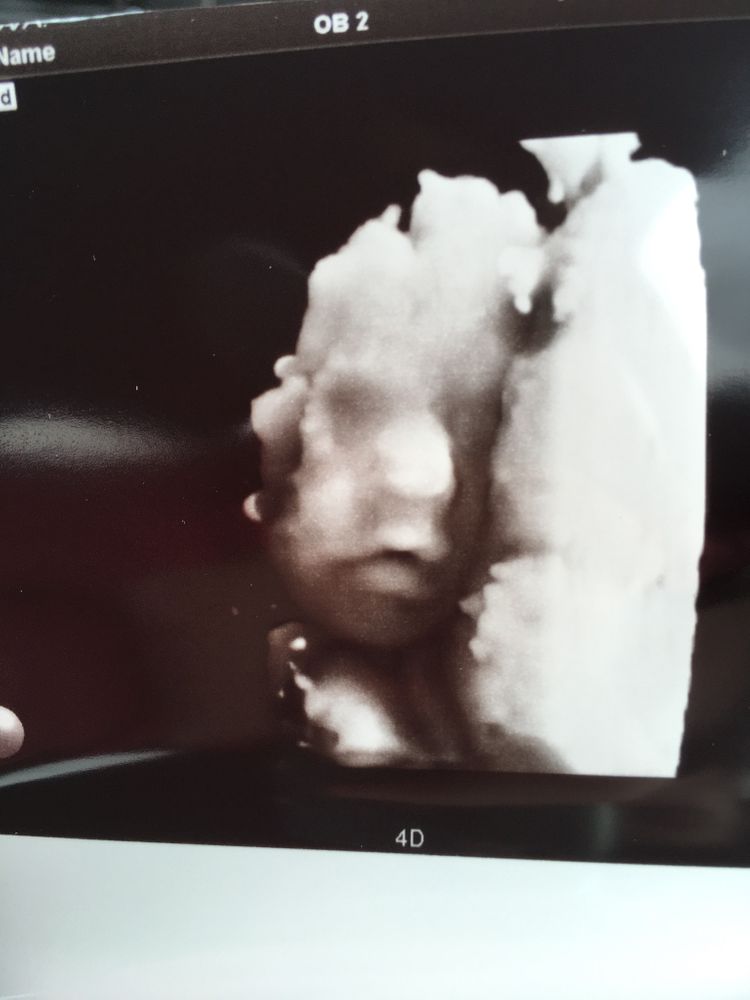

В 34 недели делала) хорошее фото получилось😍с щёчками☺️

27.05.2022